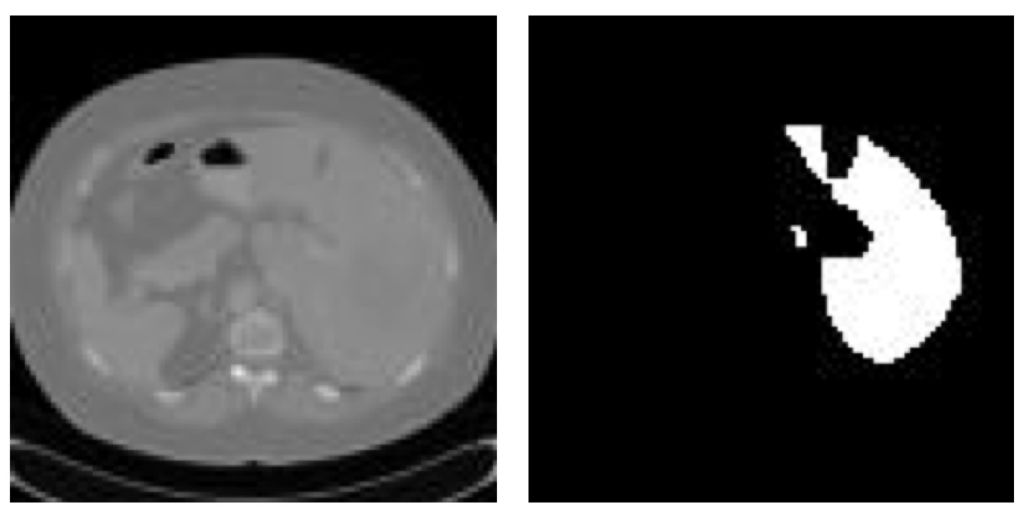

医学图像-肝脏CT

与自然图像相比,医学图像的内容和信息密度通常较低,因此医学影像的结构相对固定,语义信息也较为简单。常见的医学影像类型,比如CT、MRI、超声、病理切片和OCT等等,大多数成像方式对单一的人体器官进行成像时得到的影像结构都会相对固定一些。比如说下图的血管内超声影像,其图像特点就是官腔(lumen)的位置相较于整幅图而言永远都处于中心位置。